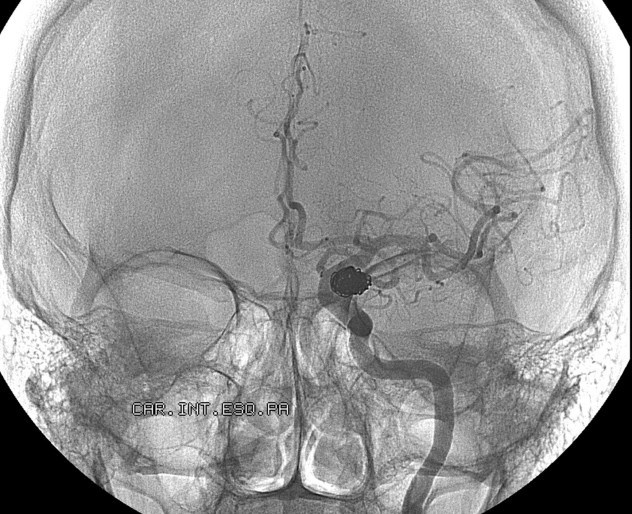

| Cục máu đông trong não của Sarah Thomson khiến cô rơi vào tình trạng hôn mê. Ảnh: BBC |

Hồi đầu năm 2012, Sarah Thomson, một phụ nữ Mỹ, đột quỵ do một cục máu đông hình thành trong não của cô. Sau khi hôn mê trong 10 ngày, cô hồi tỉnh. Song một tình trạng kỳ lạ đã xảy ra. Người phụ nữ 32 tuổi nghĩ cô đang sống trong năm 1998. Cô tưởng Spice Girls, ban nhạc mà cô thích, vẫn chưa tan rã, và cũng không biết rằng Michael Jackson đã qua đời, BBC đưa tin.